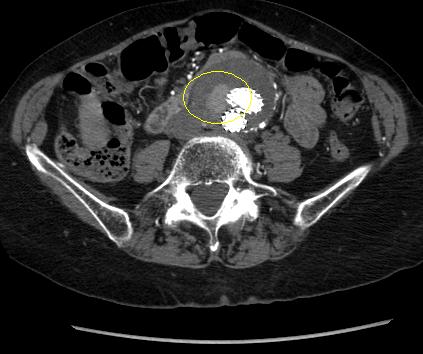

Abdominal aortic aneurysm

Type II endoleak (encircled) discovered on follow-up CT

University of Michigan, specifically the cases of Dr Upchurch reflecting the Departments of Vascular Surgery and Radiology